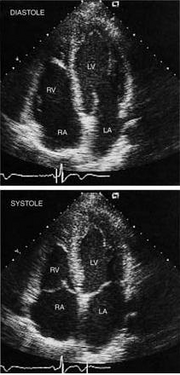

6.心尖四腔切面

(1)正常解剖结构的超声心动图表现: 图像右侧自上向下依次为左心室、二尖瓣、左房,左侧为右心室、二尖瓣、右房,中央为室间隔、房间隔。

http://webres.medlive.cn/upload/000/020/120

心尖四腔切面

(4)正常测值

①左室长径:舒张末期为7.0~8.4cm,收缩末期为5.0~6.4cm 。

②左房内径:上下径为3.1~5.3cm (收缩末期,二尖瓣环联线中点至左房顶部),横径为3.0~5.3cm。(收缩末期,心房中部)。

③右室内径:横径为2.5~4.2cm(舒张末期径),长径为5.8~7.8cm(舒张末期径)。

④右房内径为3.4~4,9cm , 横径为2.9~4,5cm (心尖四腔切面,收缩末期上下径)。

Schematic diagram of the apical four-chamber view

showing the relationships of the left and right ventricles (LV and RV) and atria (LA and RA). In the left ventricle, the papillary muscle, chordae, and anterior and posterior mitral leaflets (AMVL, PMVL) are seen. The descending aorta (DA) is seen in partial cross section lateral to the left atrium, while the right superior pulmonary vein (RSPV) drains into the left atrium adjacent to the interatrial septum. In the right ventricle, the moderator band (MBlack Eye and the anterior and septal tricuspid valve leaflets (ATVL and STVL) are seen. Note the ventriculoatrial septum (VAS) separating the left ventricle from the right atrium in association with the normal, slightly more apical position of the tricuspid compared with the mitral valve annulus.

Two-dimensional echo images in an apical four-chamber view at end-diastole (above) and end-systole (below).